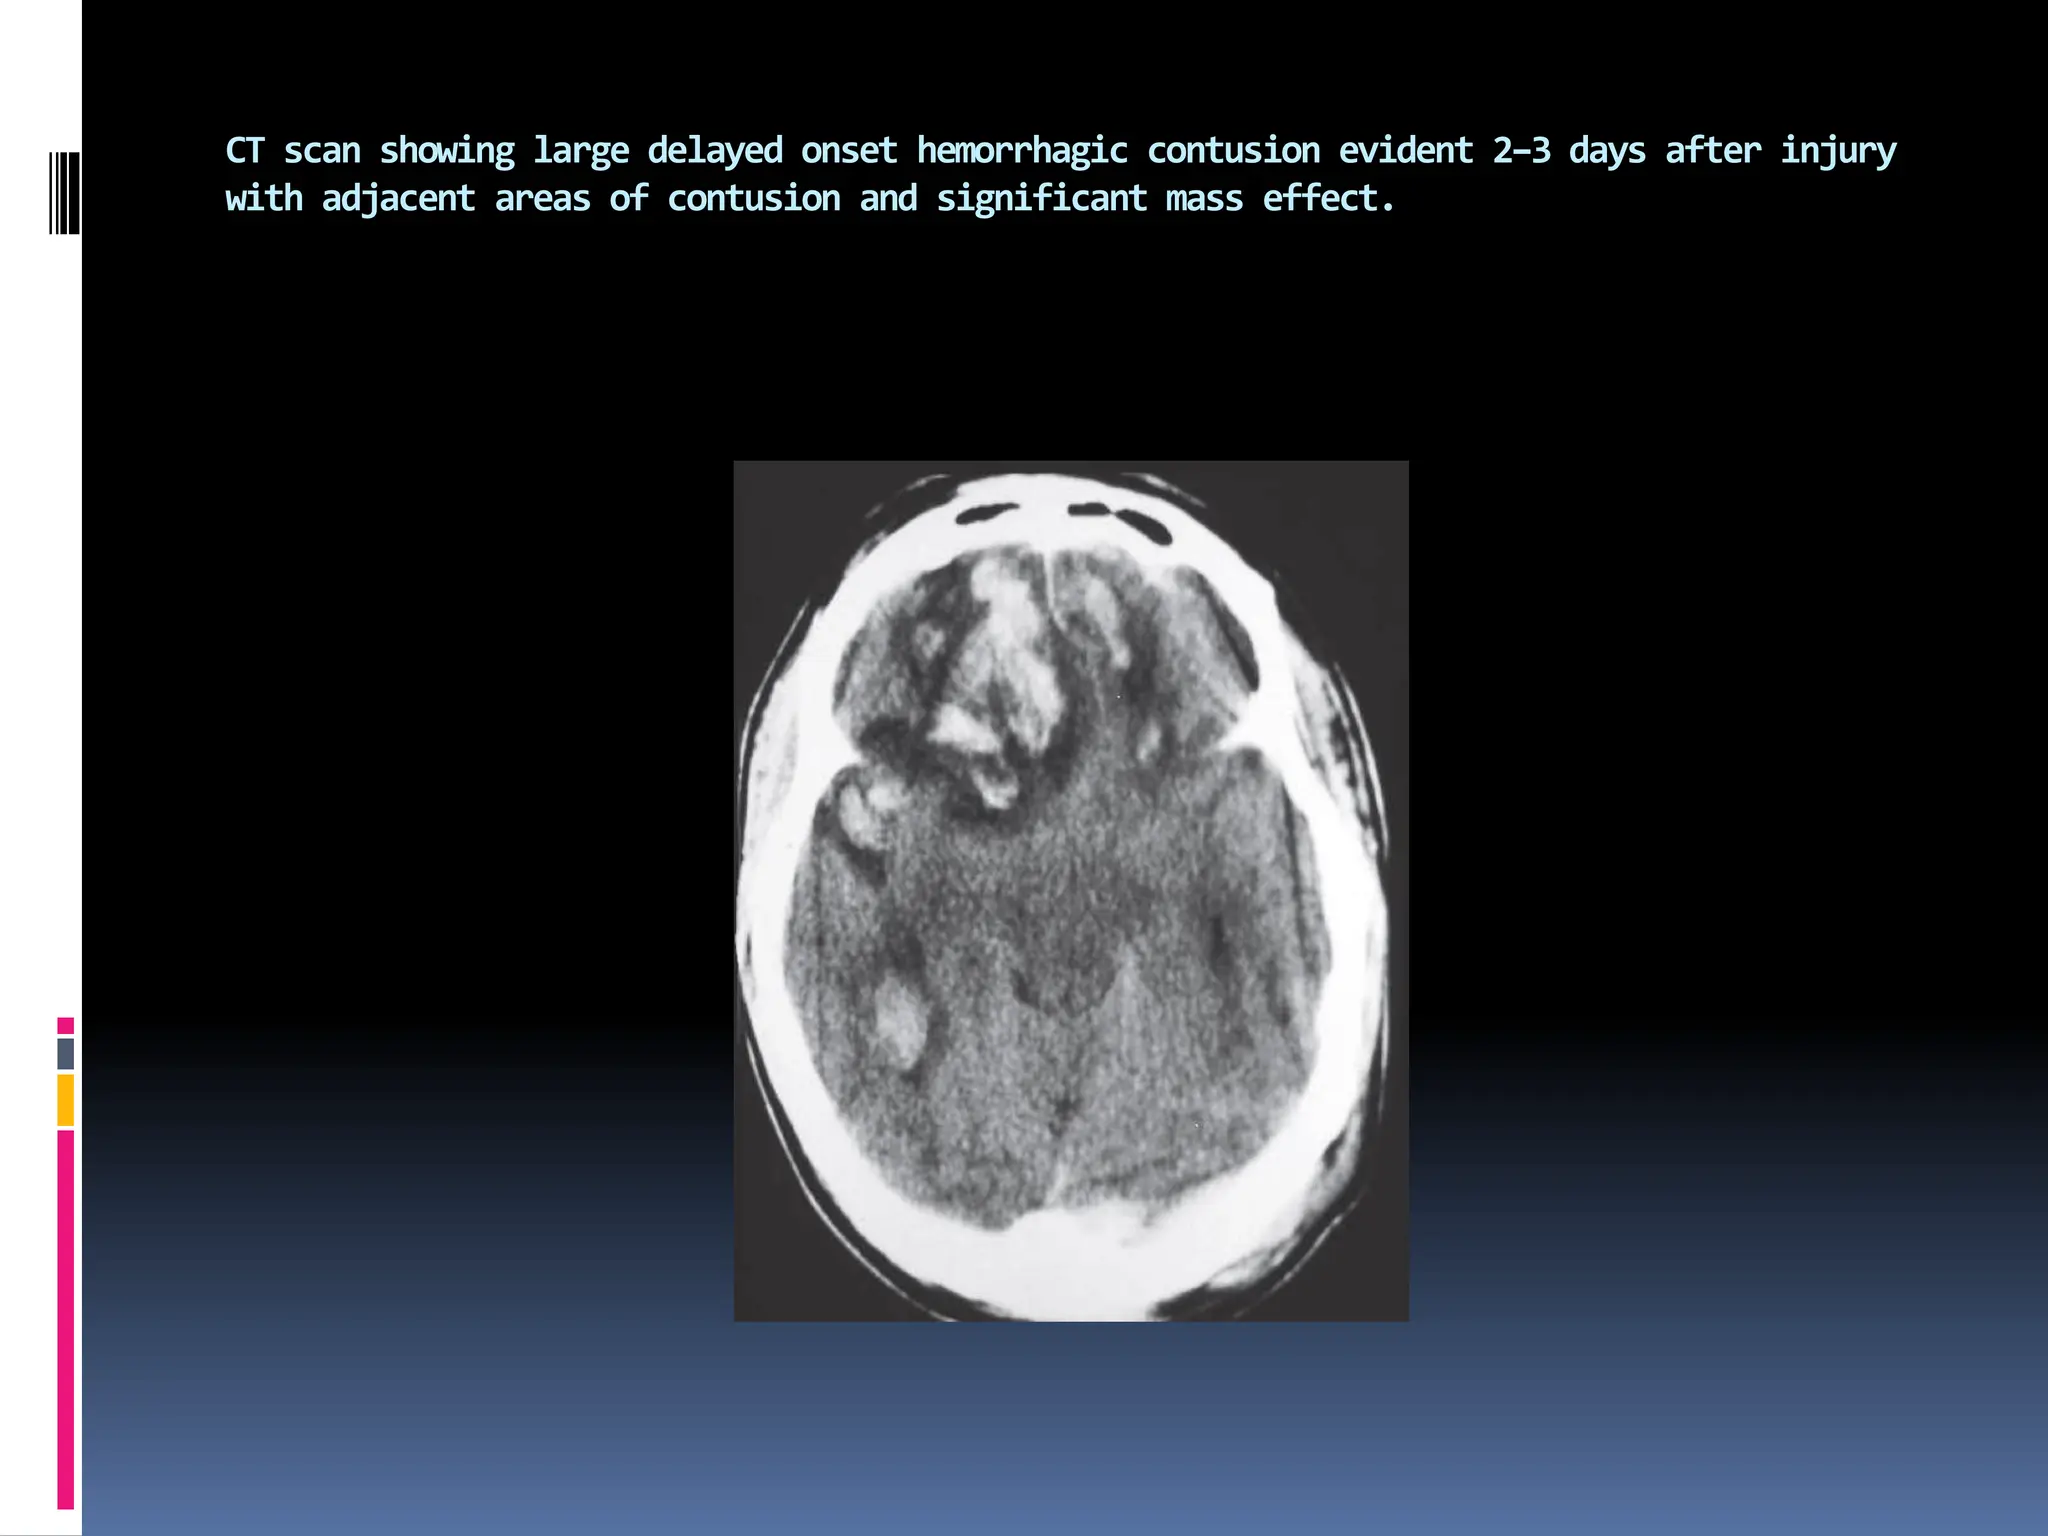

CT scan showing large delayed onset hemorrhagic contusion evident 2–3 days after injury

with adjacent areas of contusion and significant mass effect.